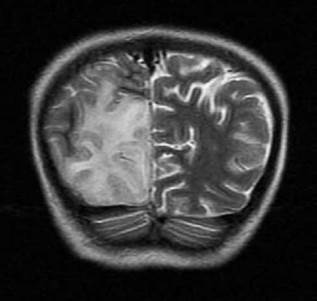

En las neuroimágenes de pacientes con síndrome MELAS se pueden encontrar lesiones cerebrales similares a un infarto cerebral isquémico -especialmente en las regiones posteriores de los lóbulos temporales, parietales y occipitales- pero que superan un territorio vascular; de igual forma, son evidentes las calcificaciones cerebrales en ganglios basales y la atrofia cerebral desproporcionada para la edad del paciente,9 tal como se corroboró en el caso descrito (Figura 2).